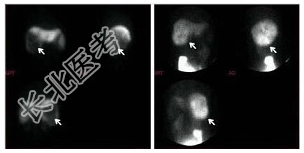

- [材料题] 男性,48岁,上腹部不适,AFP阴性,行⁹⁹Tcᵐ-Phy及⁶⁷Ga-枸橼酸钠显像如图:

- 简答题1、可能的诊断是?

- 简答题2、如果AFP阳性,对诊断有何影响?如果持续阴性,又该如何进一步明确诊断?